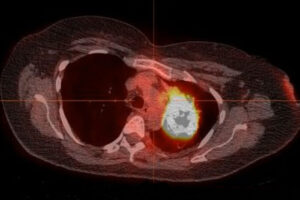

Targeted therapy shrank tumors, shows promise in improving survival